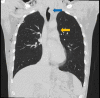

Tracheobronchial injury (TBI) is a rare life-threatening injury that can result from either penetrating or blunt trauma. Treatment may be surgical or conservative, but the evidence regarding which is the best approach is still very scarce. This case report describes the successful conservative management of a 32-year-old male with a traumatic tracheal laceration. The alarming signs and symptoms, the imaging modalities of choice, the rationale behind the treatment strategy, and the most common complications are detailed here. Through this case, the authors wish to highlight the features that should lead to the suspicion of this potentially fatal traumatic injury, as well as raise awareness on how to adequately manage these patients.